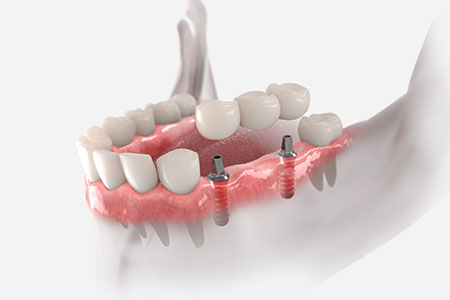

骨の弱い方や、骨が柔らかい方には、インプラント6本で歯を支えるオールオン6がお勧めです。

オールオン6とは、6本のインプラントで12本の歯を支える治療方法です。

この方法は、日本人のように顎の骨が比較的やわらかいケースで採用されることが多く、オールオン4との主な違いは、使用するインプラントの本数が4本か6本かという点にあります。

そのため、オールオン4を希望される患者さんでも、骨の状態によっては6本のインプラントで治療を行う方が、より安定して長く使用できる場合があります。